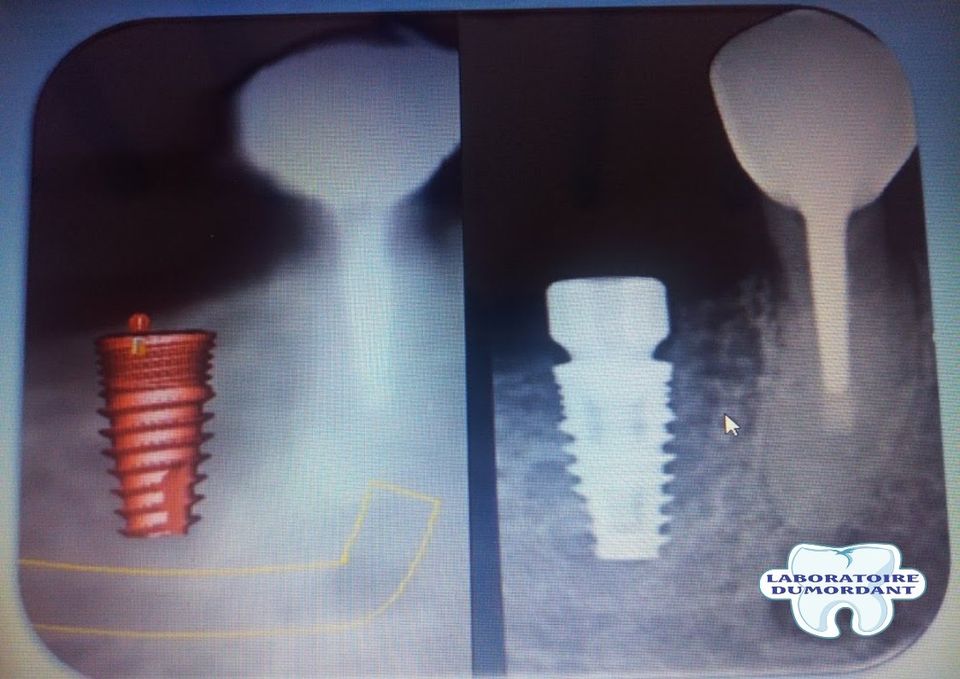

Planification implantaire

Nous travaillons avec deux logiciels de planification implantaire pour répondre à toutes les demandes.

Nous réalisons des guides chirurgicaux pour déterminer la position des futurs implants avec précision et ainsi éviter soigneusement les obstacles anatomiques tels que les nerfs ,sinus,kists, artères,racines,chevauchement/collision d'implants etc...

-Nous pouvons également matcher votre dicom avec notre stl et vous pouvez grace à une application 3D téléchargeable (android/apple/windows) visualiser simplement le futur implant avec les densités osseuses et ainsi vous préparer psychologiquement avant l'intervention chirurgicale .

Controle radio